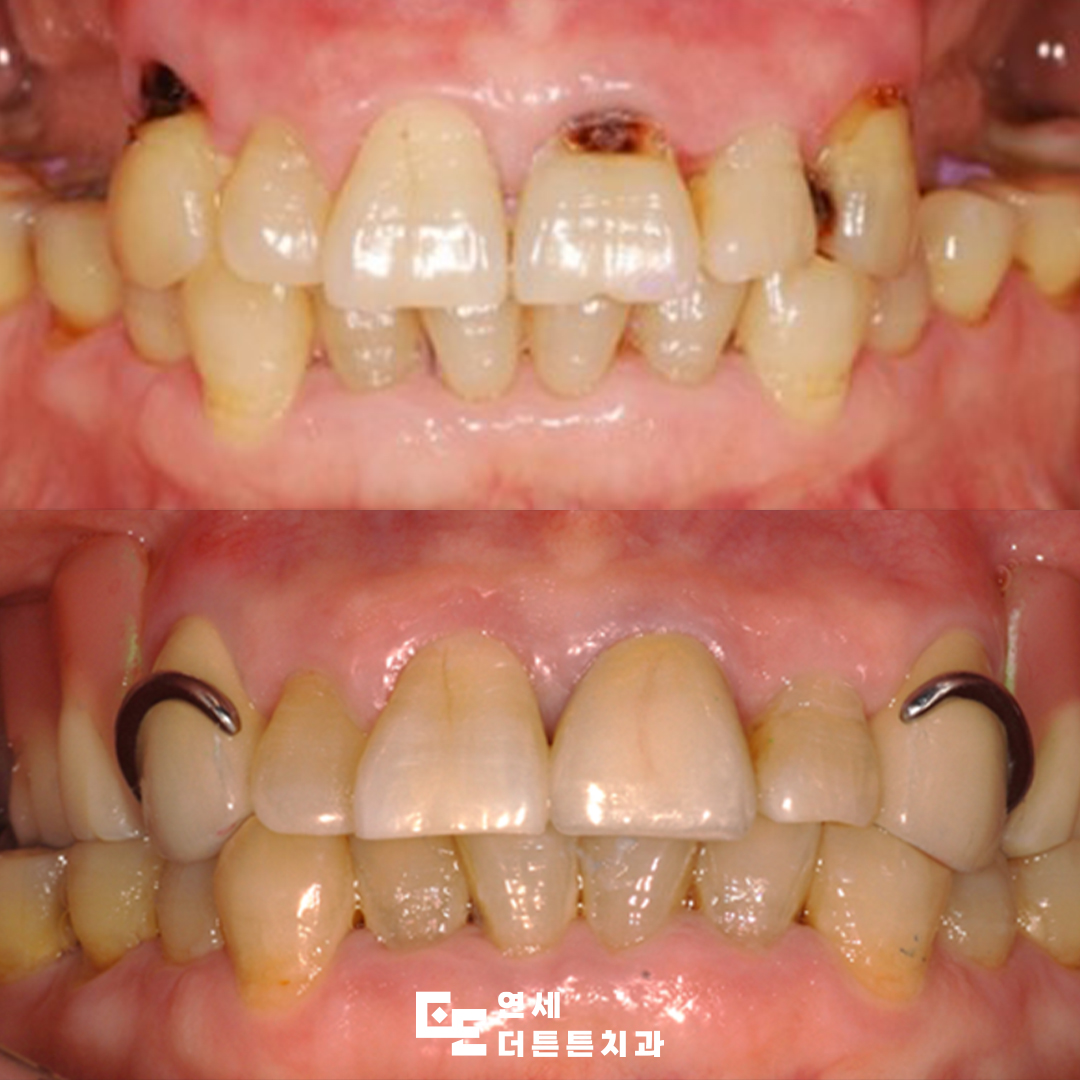

먼저 크라운 수복 후 사진입니다.

치료 완료 후의 모습입니다.

어금니의 지지 확보를 통한

앞니의 배열 관계까지 정상화하였습니다.

환자분께서도 심미적으로도

기능적 만족도 매우 높으셨는데요.